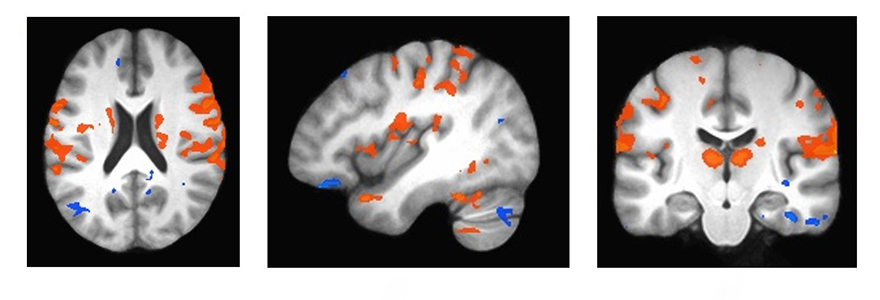

Working alongside Derek Mitchell, PhD, and Robert Bartha, PhD, and using high-field imaging systems at Robarts, Dr. Finger used fMRI brain imaging to look specifically at a network in the brain called the limbic system, which is important for emotion and reward processing. These regions are normally activated during emotional expression, however, that activity is significantly reduced in patients with FTD.

“This kind of high-field imaging, found uniquely at Robarts, can show really subtle changes in brain function,” said Bartha. “The changes found in this study help us to understand how the disease is affecting the brain, and gives us new ideas about how and when to treat these patients.”

The hope is that by finding ways to boost the activity in the limbic region in the brains of patients with FTD, it might lead to therapies to treat these deficits in emotional processing and empathy.

What the researchers found is that when they asked patients to mimic facial expressions, the brain imaging showed a change in this important region of the brain.